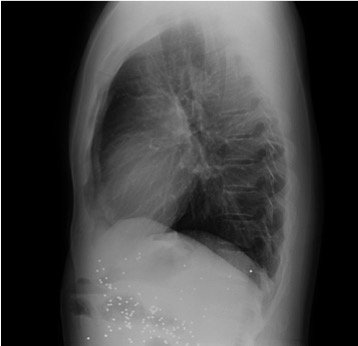

Empecemos, ¿qué ves?

- Comprobar que la placa está bien centrada e inspirada (6 arcos costales anteriores ó 9 posteriores).

- Abdomen y Diafragma

- Partes blandas y estructura ósea.

- Mediastino con silueta cardiaca.

- Parénquimas pulmonares (por separado)

- Comparar un pulmón con otro.

Seguir esta sistemática, dejando el pulmón para el final no nos olvidaremos de lo más importante.

Regla: Acaso Tiene Mucha Patología Pulmonar (Abdomen, Tejidos blandos y hueso, Mediastino, Pulmón por separado, Pulmón bilateral)

Nota: ¡¡¡No olvidar la placa lateral!!! La regla a seguir es la misma. Leer abdomen y diafragma, examinar parte posterior, tejidos blandos y subir por la columna; tráquea y descender por mediastino. Finalmente pulmones.

Solución: Es un estudio Normal. Silueta cardiomediastínica y parénquimas pulmonares sin alteraciones significativas.